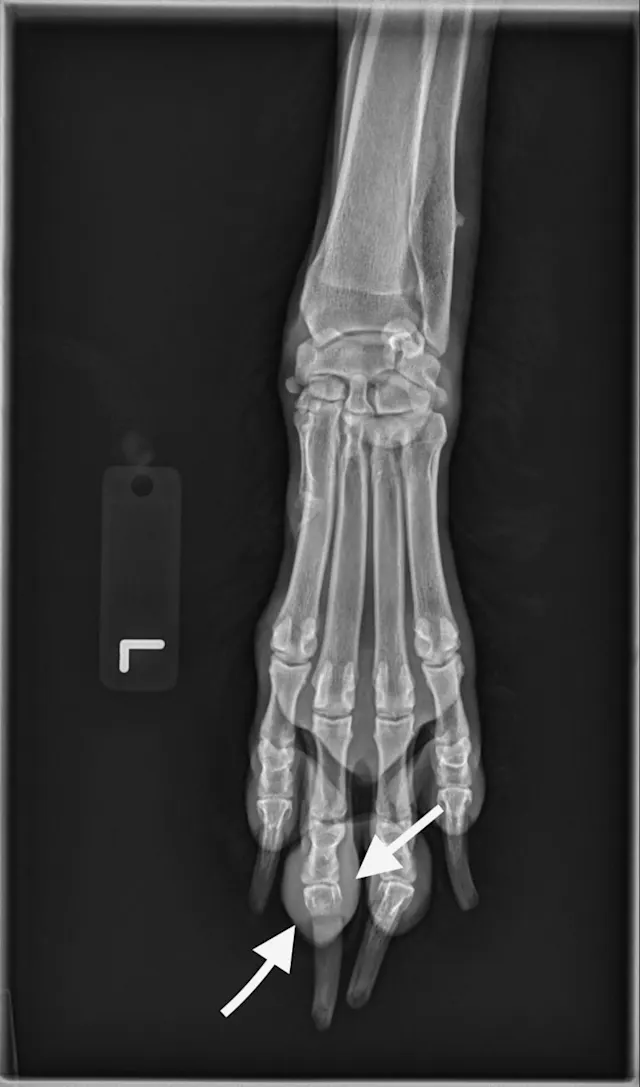

Digit melanoma

A single craniocaudal radiograph illustrates the forepaws of a 12-year-old neutered male Airedale terrier with digit melanoma. Moderate circumferential soft tissue swelling of the 5th digit of the left thoracic limb and significant lysis of the distal phalanx can be noted (arrows). The aggressive monostotic lesion of the distal phalanx of the 5th digit and associated soft tissue swelling are consistent with digital melanoma, which was confirmed via histopathology after digit amputation.